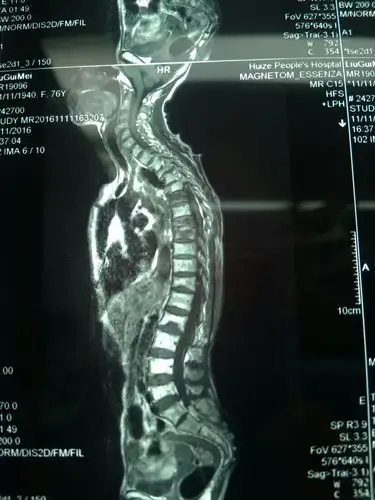

术前核磁共振

我院骨三科成功完成长阶段胸椎后壁切除减压手术一例

严重上胸椎黄韧带骨化,胸椎管狭窄治愈 - 好大夫在线

胸椎mri

mri胸椎压缩性骨折

核磁共振检查可以看出椎体骨折是否是新鲜及陈旧性.